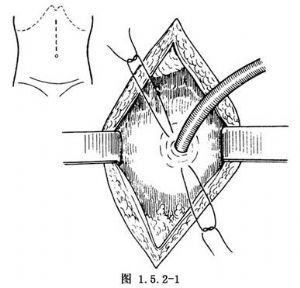

这是最简便的一种暂时性胃造口术。取平卧位,做上腹部中线或左上腹直肌切口。进入腹腔后,将胃体部置于手术野中,一般选择在胃体部前壁胃大弯小弯的中点处造口。用湿纱布垫覆盖于手术野四周,保护腹腔防止污染。用细的不吸收线于预定造口处做一荷包缝合。于荷包缝合的中央切开胃壁全层,切口大小以正好置入导管为度。用F14~16号导尿管或乳胶管经此切口插入胃腔3~5cm,亦可用蕈状导管或带气囊的导管插入,以防脱出。收紧结扎荷包缝合线使浆膜内翻紧贴导管。于第1个荷包缝合线外1~1.5cm处再做一荷包缝合并收紧结扎。必要时可做第3层荷包缝合(图1.5.2-1)。于切口左侧腹壁戳一小口,将导管经此口拖出。造口周围的胃壁与腹壁戳口四周的腹膜固定缝合3或4针,应无张力(图1.5.2-2)。最后将导管固定缝合于皮肤,按层缝合切口(图1.5.2-3)。